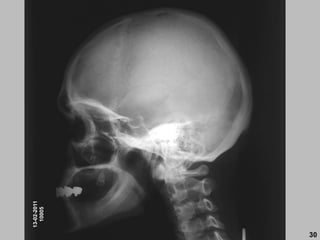

13-02-2011

10005

30